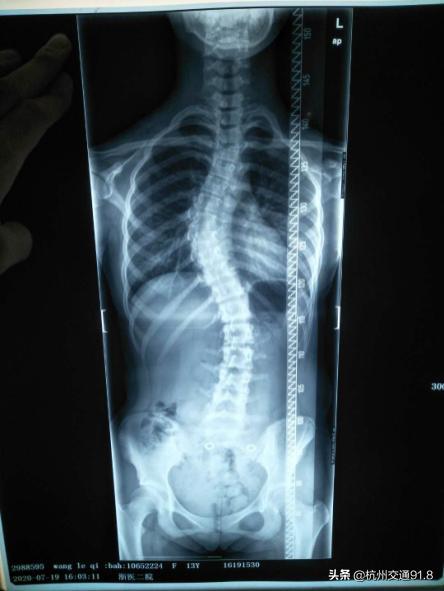

无独有偶,浙大医学院附属市一医院针灸推拿科最近也来了一个13岁的小姑娘,和晨晨可谓“难姐难妹”。爸妈也是无意间发现她总是斜着身子走路,结果来医院一查,发现脊柱侧弯已经成了“S”型。

病例X光照片